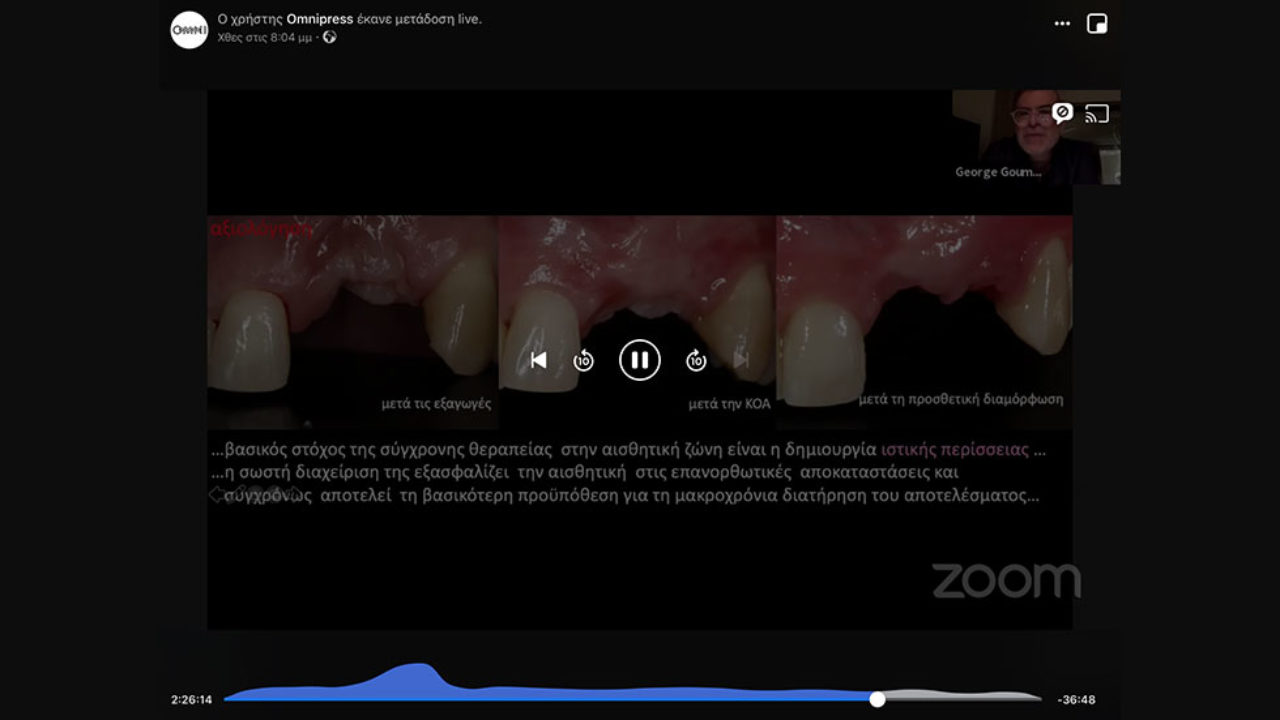

Πρόκειται για την περίπτωση μιας γυναίκας 38 ετών με χρόνια γενικευμένη περιοδοντίτιδα μετρίας βαρύτητας με εντοπισμένες περιοχές προχωρημένης #26,47 (Εικ.1), ελεύθερο ιατρικό ιστορικό, μη καπνίστρια, η οποία προσήλθε στο ιατρείο θέλοντας να φτιάξει το χαμόγελο της[1].

Ο Γεώργιος Γούμενος παρουσίασε βήμα βήμα φωτογραφίες και εξηγώντας ταυτόχρονα σε όσους συμμετείχαν στο webinar πώς και γιατί οδηγήθηκε σε αυτές τις επιλογές. Η διάρκεια του webinar ήταν κοντά στις 3 ώρες, μιας και… το πάθος για την οδοντιατρική δεν περιορίζεται!